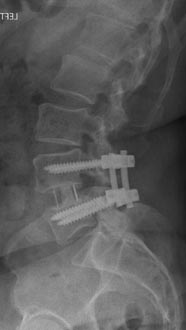

61 year old man with previous history of microdiscectomy at L4-5 presenting with severe back pain with radiating pain down the right leg with weakness. He had a massive disc extrusion on the right side. Options included revision discectomy vs. L4-5 revision decompression and fusion with transforaminal lumbar interbody fusion (TLIF). Patient did not want to go through the pains of recurrent disc herniation again and elected for the fusion.